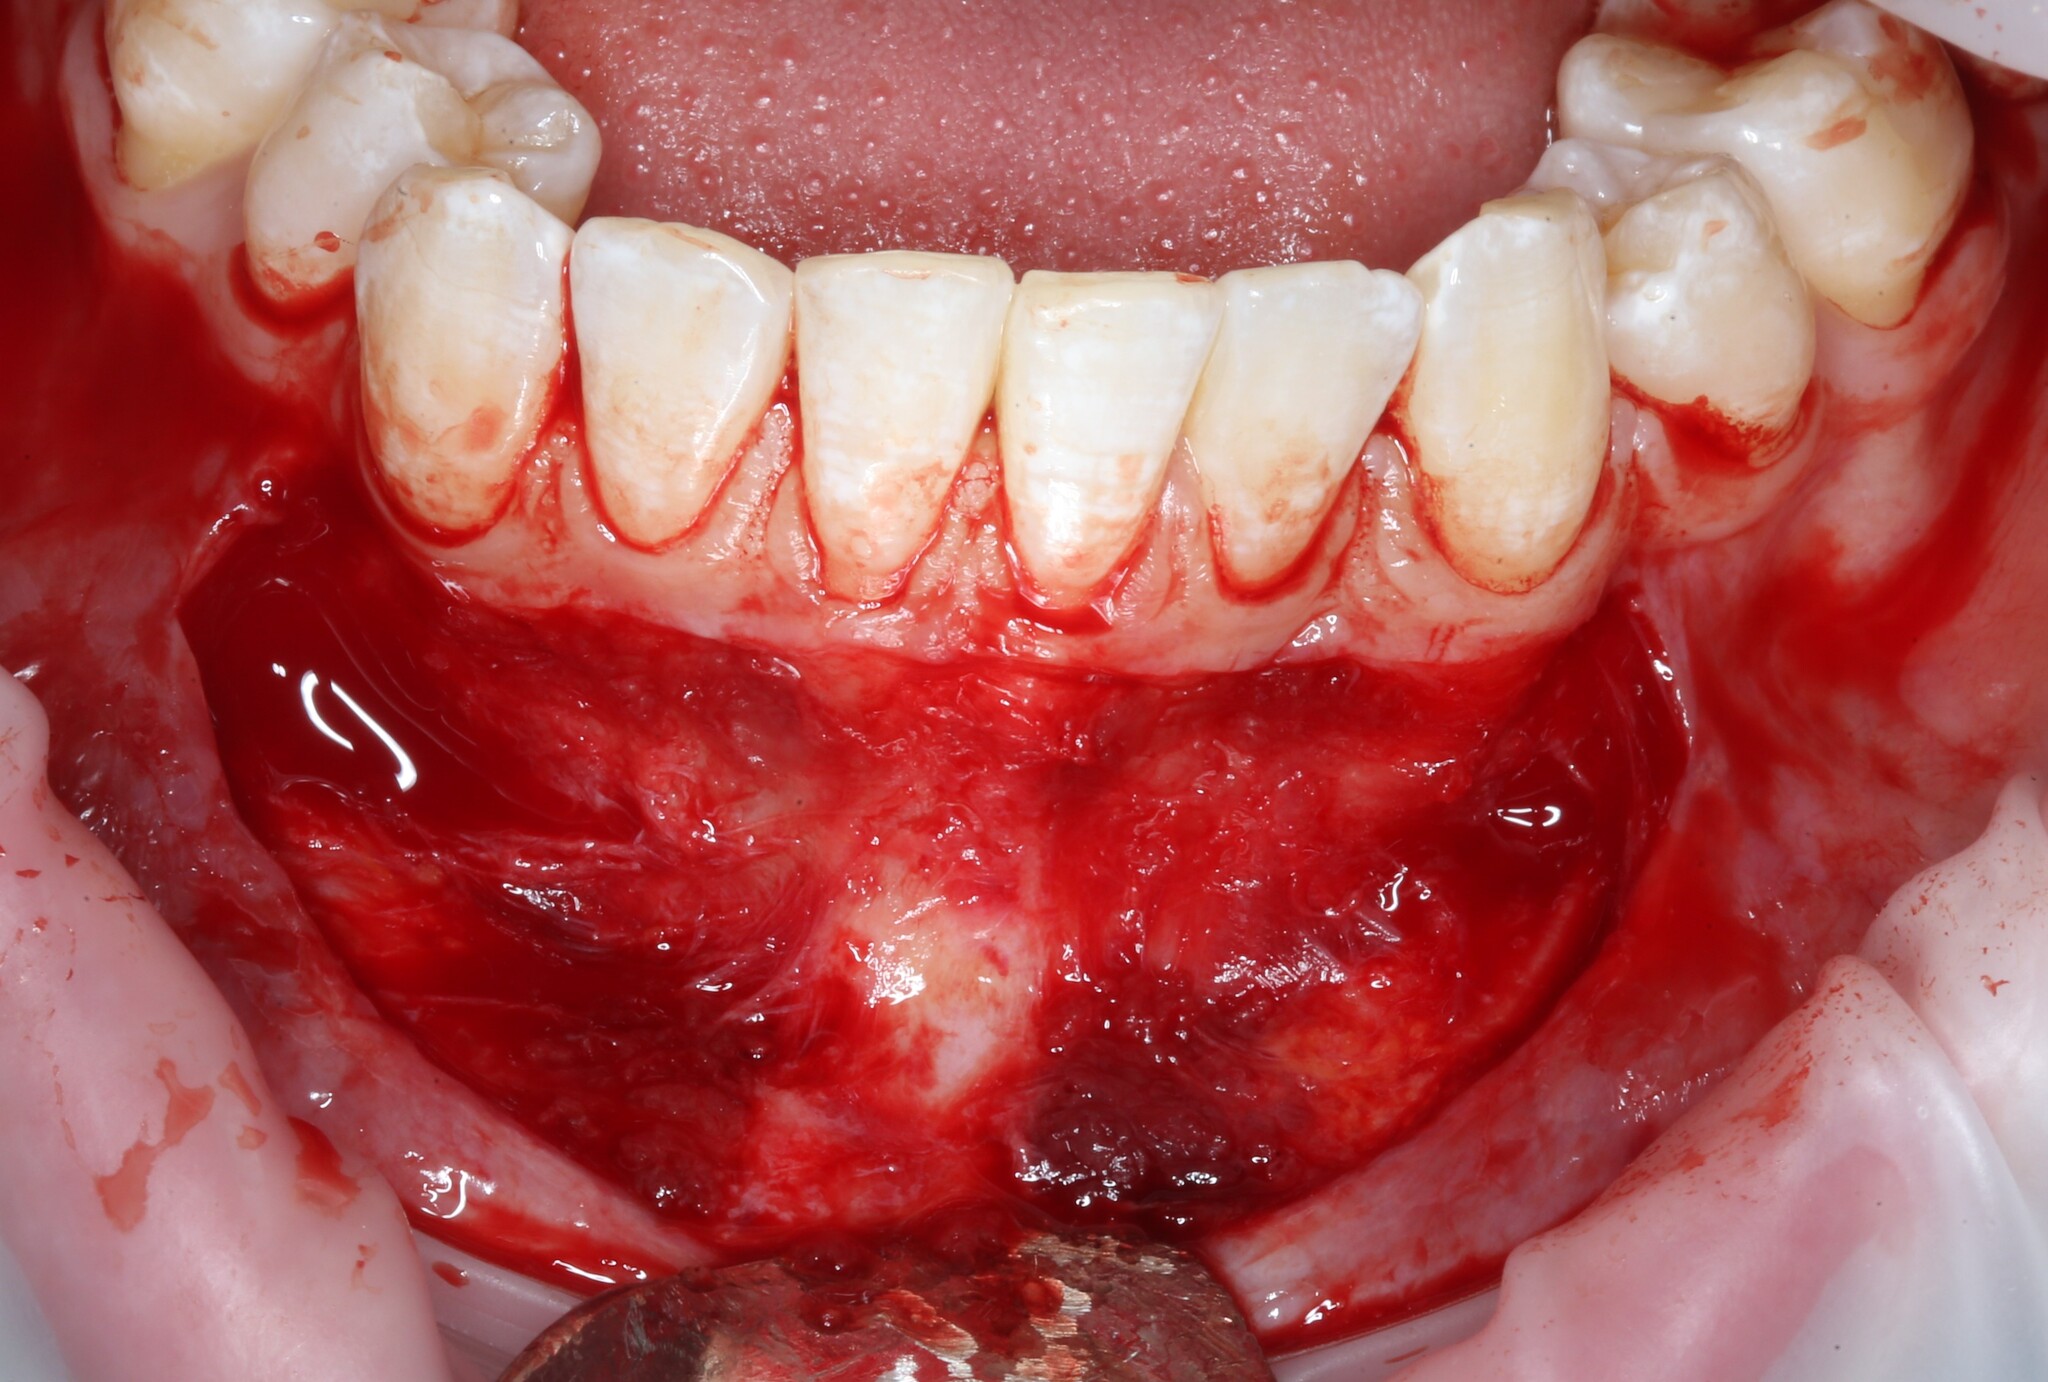

После проведенной анестезии границы слизистых видно отчетливее:

Там, где «вздулось», – подвижная слизистая оболочка, где нет – прикрепленная десна.

Разрез проводится как раз на их границе:

Разрез необходимо делать не до кости, а до надкостницы.